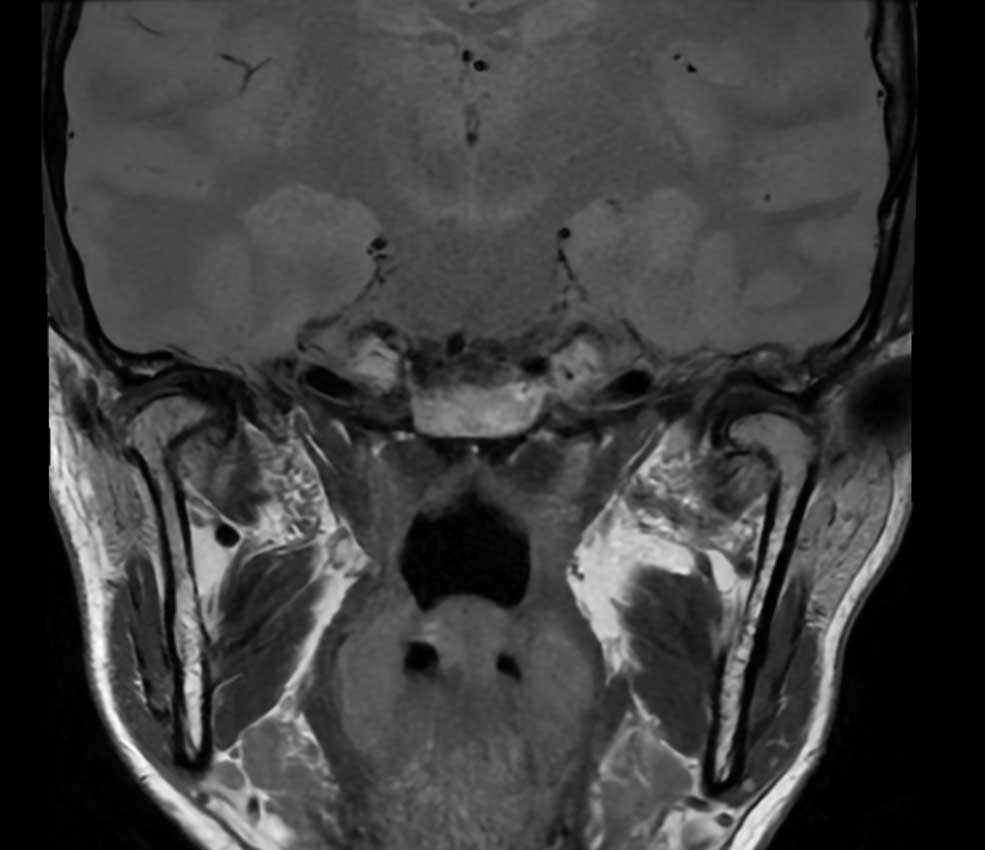

Die Magnetresonanztomographie (MRT) des Kiefergelenks ist ein fortschrittliches diagnostisches Verfahren, das Strukturen im Kiefergelenksbereich detailliert darstellt. Dieses Verfahren hat sich als äußerst wertvoll für die Beurteilung von Kiefergelenkserkrankungen, – verletzungen und Funktionsstörungen erwiesen.

Die MRT des Kiefergelenks ermöglicht es Ärzt:innen, eine genaue Beurteilung dieser Strukturen vorzunehmen, um Erkrankungen wie Kiefergelenksentzündungen (Arthritis), Diskusverlagerungen, Degeneration von Knorpel und Knochen, Kiefergelenkblockaden und andere Störungen zu identifizieren.

Eine MRT des Kiefergelenks kann zur Diagnose verschiedener Zustände wie Kiefergelenksarthrose, Diskusverlagerungen, Entzündungen, Verletzungen und Tumoren eingesetzt werden. Es bietet detaillierte Einblicke in die Strukturen und ermöglicht eine genauere Beurteilung im Vergleich zu anderen Bildgebungsmethoden.